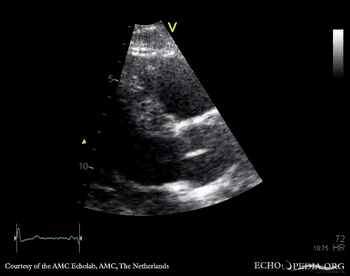

E00416.gif E00417.gif

PLAX: vegetation on aortic valve PSAX: vegetation on aortic valve